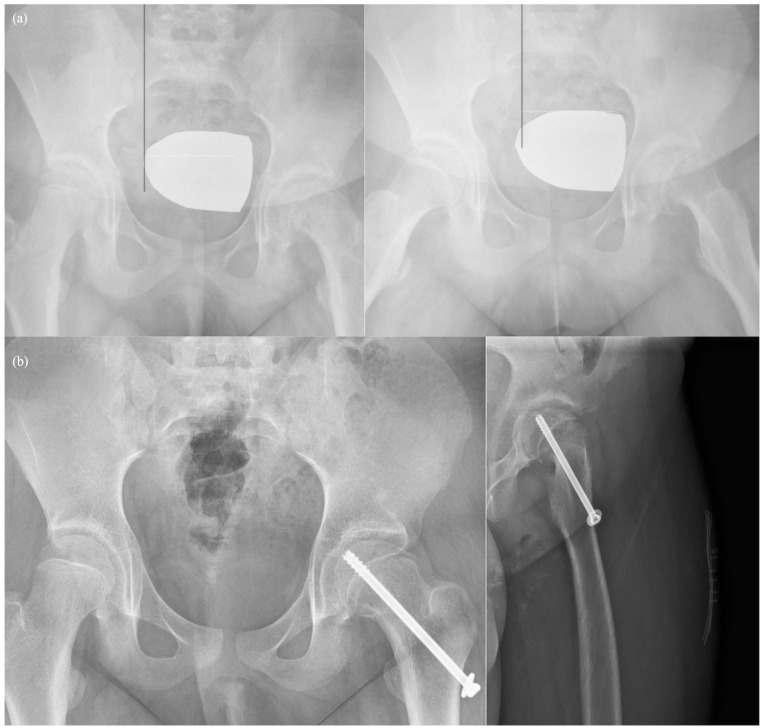

Purpose: The study aimed to compare the clinical and radiologic results of in situ pinning and modified Dunn procedure methods in stable-moderate slipped capital femoral epiphyses surgery.

Methods: Slipped capital femoral epiphyses cases between January 2000 and December 2022 were retrospectively analyzed. Stable and moderate cases treated with in situ pinning or modified Dunn procedure and those with a follow-up period longer than 1 year were included. Two groups were formed: the in situ pinning group and the modified Dunn procedure group. Radiologically, postoperative alpha angle, Southwick angle, avascular necrosis, and osteoarthritis rates were compared. Clinically, Harris Hip Score and Merle d'Aubigné score were compared. Total complications were evaluated.

Results: The in situ pinning group consisted of 28 patients and the modified Dunn procedure group consisted of 17 patients. The groups were similar in terms of age, gender, affected side, body mass index, Fahey/O'Brien Classification, preoperative slip angles, and follow-up time. Operation time was shorter in the in situ pinning group (p < 0.001). Postoperative Southwick and alpha angle were lower in the modified Dunn procedure group (p < 0.001). In clinical outcomes, Merle d'Aubigné and Harris Hip Score were higher in the in situ pinning group (p = 0.013, p = 0.005, respectively). The rate of avascular necrosis was higher in the modified Dunn procedure group (p = 0.048). There was no difference between the groups in terms of total complications and osteoarthritis.

Conclusions: In situ pinning has an advantage over the modified Dunn procedure in the treatment of stable-moderate slipped capital femoral epiphyses due to shorter operative time, better clinical outcomes, and fewer avascular necrosis rates. Although Southwick and alpha angle measurements were found to be higher after in situ pinning compared to the modified Dunn procedure, this does not constitute a significant disadvantage in terms of osteoarthritis development in the mid-term.